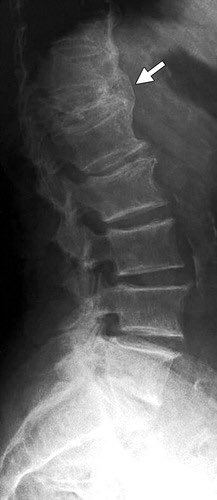

اسئله كثيره توصلني بخصوص هشاشة العظام

اسبابه؟

التشخيص ؟

العلاج؟

الوقاية ؟

اسئله كثيره توصلني بخصوص هشاشة العظام اسبابه؟ التشخيص ؟ العلاج؟ الوقاية ؟ #من_الخاص_روماتزم التفاصيل هنا 👇🏼 https://t.co/UTHyahGgTG